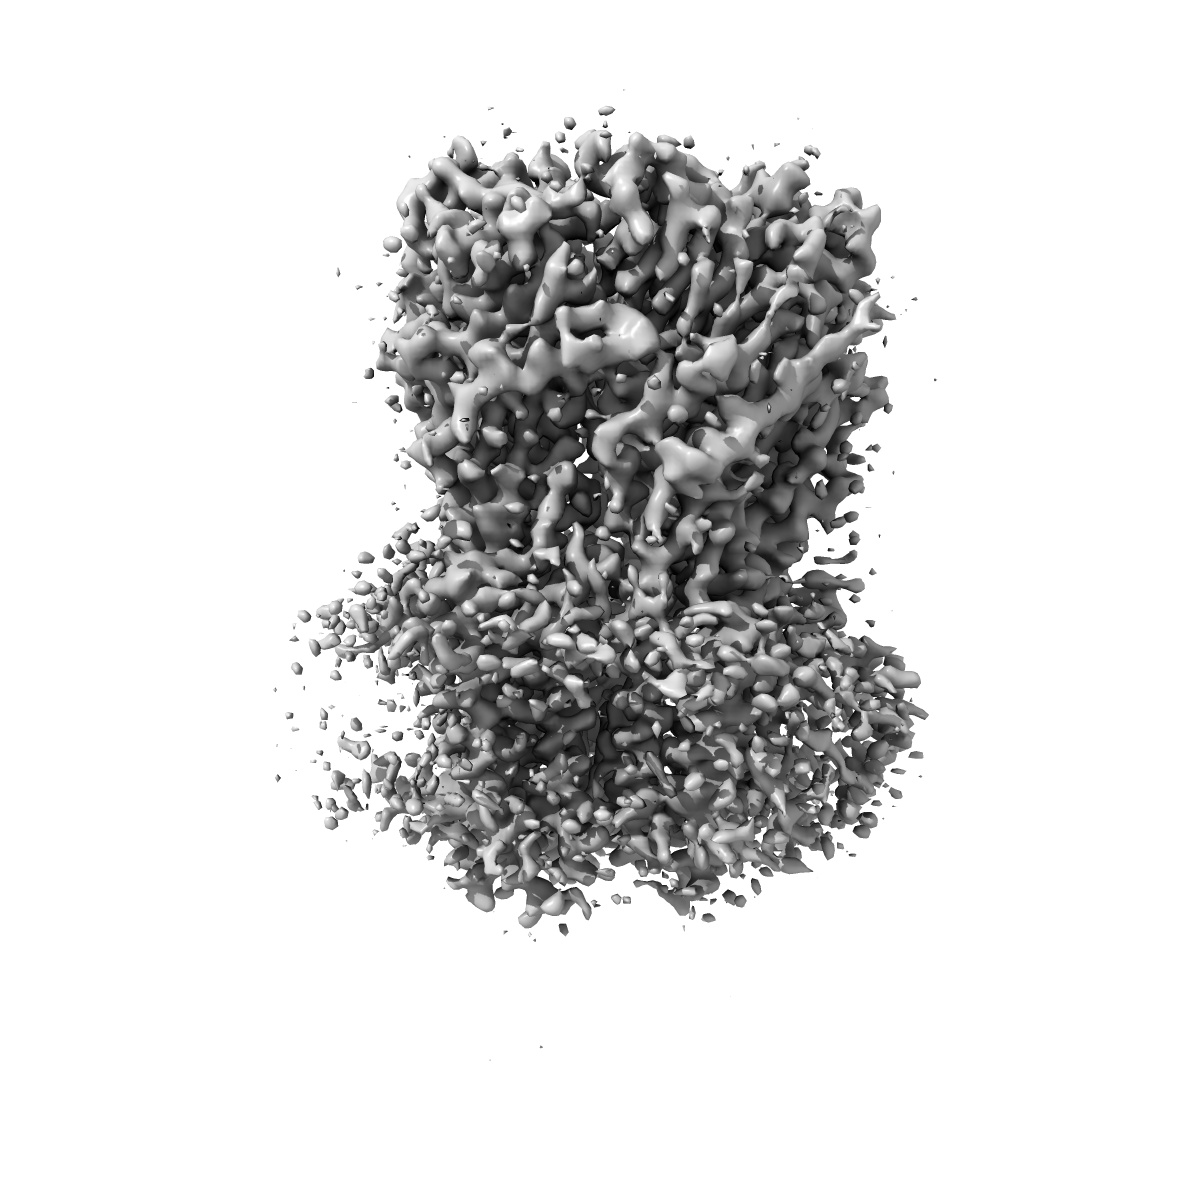

Cyro-EM structure of human Glycine Receptor alpha2-beta heteromer, glycine bound, (semi)open state

Sample: Glycine receptor alpha2-beta heteromer, glycine bound, open state

Characterization of the subunit composition and structure of adult human glycine receptors

Yu H, Bai X-C, Wang W

(2021) Neuron , 109 , 2707 - 2716